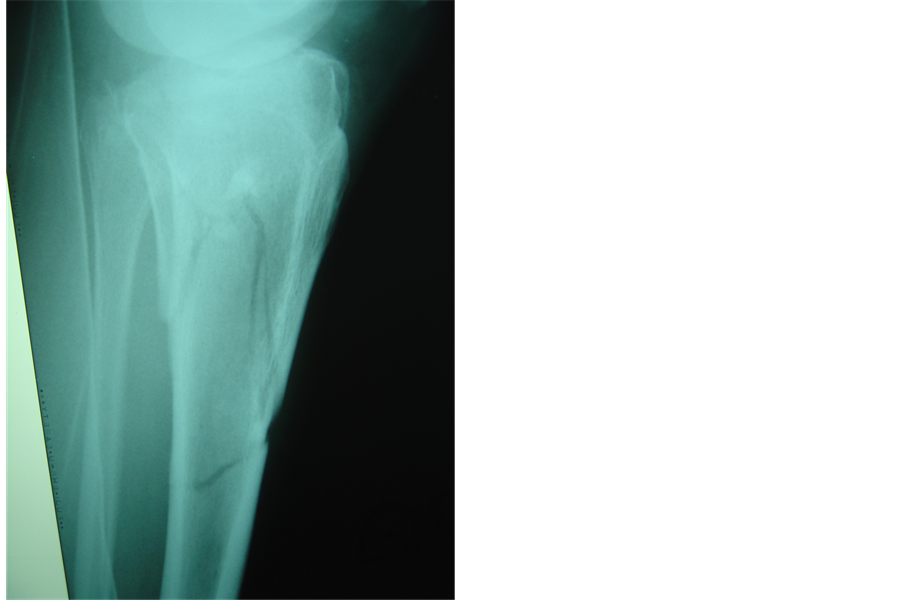

Operation was performed under epidural anesthesia. Preoperative assessment of radiographs and computerized tomography scans helped us achieve a good perspective of the fracture components. A tourniquet was applied only if the open method was to be used. Initially, when necessary, the knee hematoma was aspirated. Operation was then carried out under II control and always started with the application of one or more 6.5 millimeter canulated screws with washers, usually from the lateral side, parallel and as close to the articular surface as possible. At this stage, if needed, the articular surface was elevated by the use of a guide pin. Thus, the tibial plateau were reduced and compressed. Fixation was then completed with application of a hybrid external fixator (bridging the knee if required) or less invasive internal fixation with a limited lateral approach and an anatomic locking plate. Manual traction and various instruments (an owl or a large tenaculum reduction forceps or a tractor or use of a k-w like a joystick) were used to reduce the condyles [6] . Varus or valgus angulation was assessed very carefully and corrected. We did not perform ligament or meniscus repairs. All fractures were reduced with the knee closed. In case of instability, the knee was bridged with an extension of the hybrid to the lateral side of the femur [7] . We used a full ring, parallel to the articular surface and centered over the tibia, allowing close to 90˚ of knee flexion. We always applied two wires forming an x in axial viewing. These wires were placed within anatomically safe zones at the typical positions (posterolateral to anteromedial tibia through the head of the fibula and anterolateral to posteromedial). Then a third wire was inserted, usually between the first two and parallel to the articular surface in the AP view, but occasionally parallel and above the second one.. If an olive wire were used, it was inserted until the olive contacted the bone surface to apply extra compression. The wires were then fixed to the ring and tensioned. Three peripheral pins were applied, the fixator mounted and the fracture finally manipulated, reduced and stabilized (Figures 1(a)-1(d), Figures 2(a)-2(d)).

Figure 1. (a), (b): Scatzker VI fracture. Pre operative X-rays AP and Lateral; (c), (d): Same fracture treated with combination of hybrid external fixator with one percutaneous canulated screw. Post operative X-rays AP and Lateral.